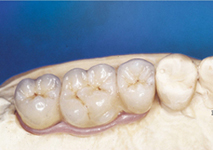

Pevné můstky – lepené nebo šroubované

S pomocí zubních implantátů můžeme díky různým kotevním systémům (třmeny, kulové hlavy, Locatory) zajistit stabilitu a držení protézy nebo při použití většího počtu implantátů zhotovit pevné náhrady – můstky nalepené nebo našroubované na pevno na implantáty.

S těmito typy náhrad můžeme dosáhnout perfektní funkci, výbornou estetiku, fonetiku a současně zajistit u pacienta možnost dobré hygienickou péče a čištění, která je pro životnost implantátů velice důležitá.